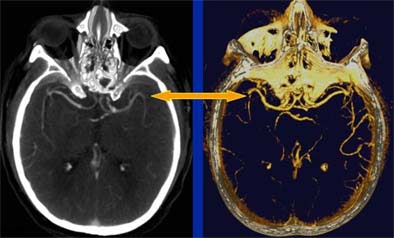

| Head CT seen in slab MIP (maximum intensity projection) view (left), and volume-rendered view (right) depict M2 artery occlusion. Images courtesy of Dr. Jay Cinnamon. |